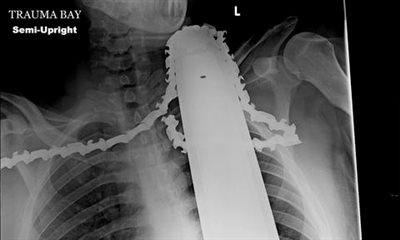

Πήγε στο νοσοκομείο με ένα αλυσοπρίονο καρφωμένο στο λαιμό του

Ο Τζέιμς Βαλεντάιν, 21 χρονών, μαζί με τους συνεργάτες του κλάδευαν δέντρα το απόφγευμα της Δευτέρας, όταν το αλυσοπρίονο του ξαφνικά έστριψε και καρφώθηκε στο λαιμό του.

Οι συνάδερφοί του τον κατέβασαν από το δέντρο και τον μετέφεραν στο Γενικό Νοσοκομείο του Πίτσμπουργκ.

Οι γιατροί αφαίρεσαν αρχικά το μοτέρ του πριονιού, αλλά άφησαν τις λεπίδες στο λαιμό του και τον ώμο για να αποφευχθεί πρόσθετη απώλεια αίματος, δήλωσε σύμφωνα με το ethnos, η χειρούργος Κριστίν Τόεβς.

Ευτυχώς για τον κύριο Βαλεντάιν , η λεπίδα δεν έφτασε μέχρι την καρωτίδα του και το μεγαλύτερο μέρος της ζημιάς προκλήθηκε στους μύες του ώμου.